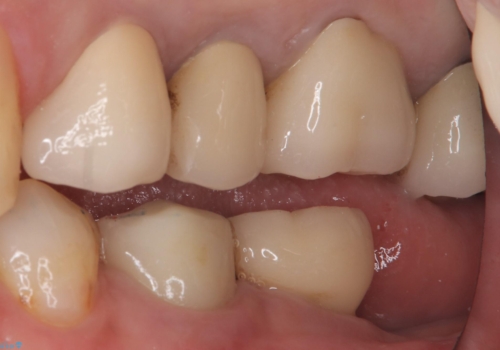

- 主訴:昔入れた被せものの境目の黒いところが気になる

クラウンの不適により境目に汚れが溜まり、黒く見えていました。

適合の良いクラウンへやり替えることとしました。

古いクラウンを除去し、不適部位から中で広がっていたカリエスを除去したのちCRにて築造、仮歯を経てセラミッククラウンをセットしています。